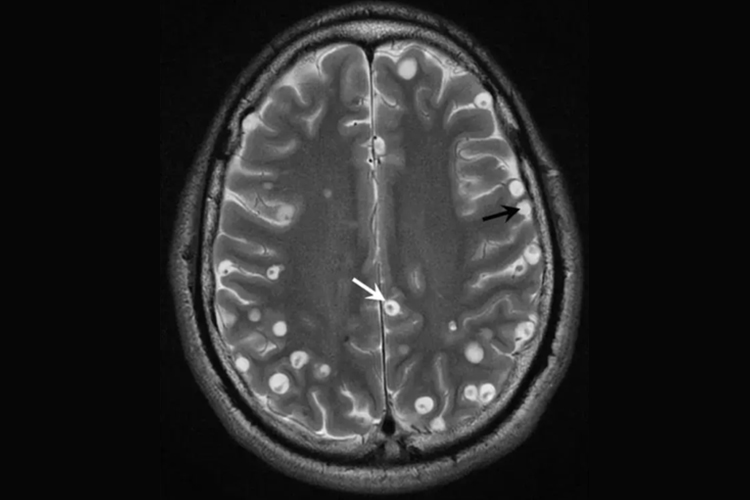

脑囊虫病:脑囊虫病的三大主要症状是癫痫发作、颅内压增高和精神症状。囊尾蚴寄生于脑实质、蛛网膜下隙和脑室,均可引起颅内压增高、神经疾患和脑血流障碍,其症状有记忆力减退,视力下降,头痛、头晕,呕吐,神志不清,失语,肢体麻木,局部抽搐,听力障碍,精神障碍,痴呆,偏瘫和失明等,脑囊虫病合并脑炎可使病变加重而致死亡。